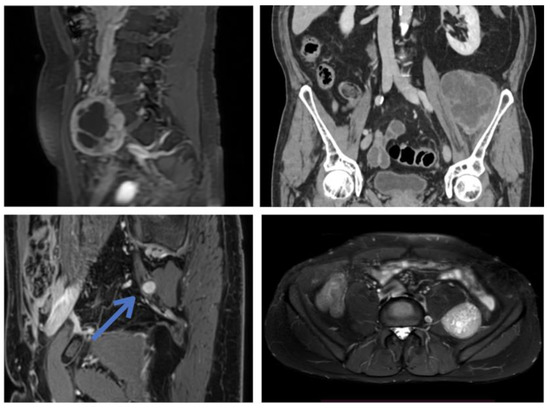

Integrated Neurosurgical Management of Retroperitoneal Benign Nerve Sheath Tumors

Peripheral nerve sheath tumors (PNST) of the retroperitoneum are rare and are often treated by general surgeons dealing with retroperitoneal cancers. However, resection without the correct microsurgical technique can cause permanent neurological deficits and pain. Here, we discuss our interdisciplinary approach based on [...] Read more.

Peripheral nerve sheath tumors (PNST) of the retroperitoneum are rare and are often treated by general surgeons dealing with retroperitoneal cancers. However, resection without the correct microsurgical technique can cause permanent neurological deficits and pain. Here, we discuss our interdisciplinary approach based on the integration of expertise from neurosurgery and abdominal surgery, allowing for both safe exposure and nerve-sparing microsurgical resection of these lesions. We present a series of 15 patients who underwent resection of benign retroperitoneal or pelvic PNST at our institution. The mean age of patients was 48.4 years; 67% were female. Tumors were 14 schwannomas and 1 neurofibroma. Eight patients (53%) reported neurologic symptoms preoperatively. The rate of complete resection was 87% (n = 13); all symptomatic patients showed improvement of their preoperative symptoms. There were no postoperative motor deficits; one patient (7%) developed a permanent sensory deficit. At a mean postoperative follow-up of 31 months, we observed no recurrences. To our best knowledge, this is the second-largest series of benign retroperitoneal PNST consistently managed with microsurgical techniques. Our experience confirms that interdisciplinary management allows for safe treatment of these tumors with good neurological and oncological outcomes. Full article